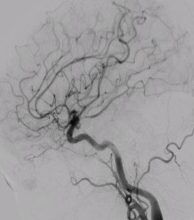

Diagnostic cerebral angiography is a special test performed to provide a map of the blood vessels in the brain. Although it is an invasive procedure, cerebral angiography is considered the best way (=gold standard) to look at the blood vessels.

- Yes, there are alternative tests that are non-invasive. These are CT angiography or MR angiography. However, the quality and information gathered from these alternatives are not as good as, especially for detecting small abnormalities. Here’s an example comparison of the resolution and information obtained: MR and CT angiography are like black and white TV versus diagnostic cerebral angiography are like color TV.